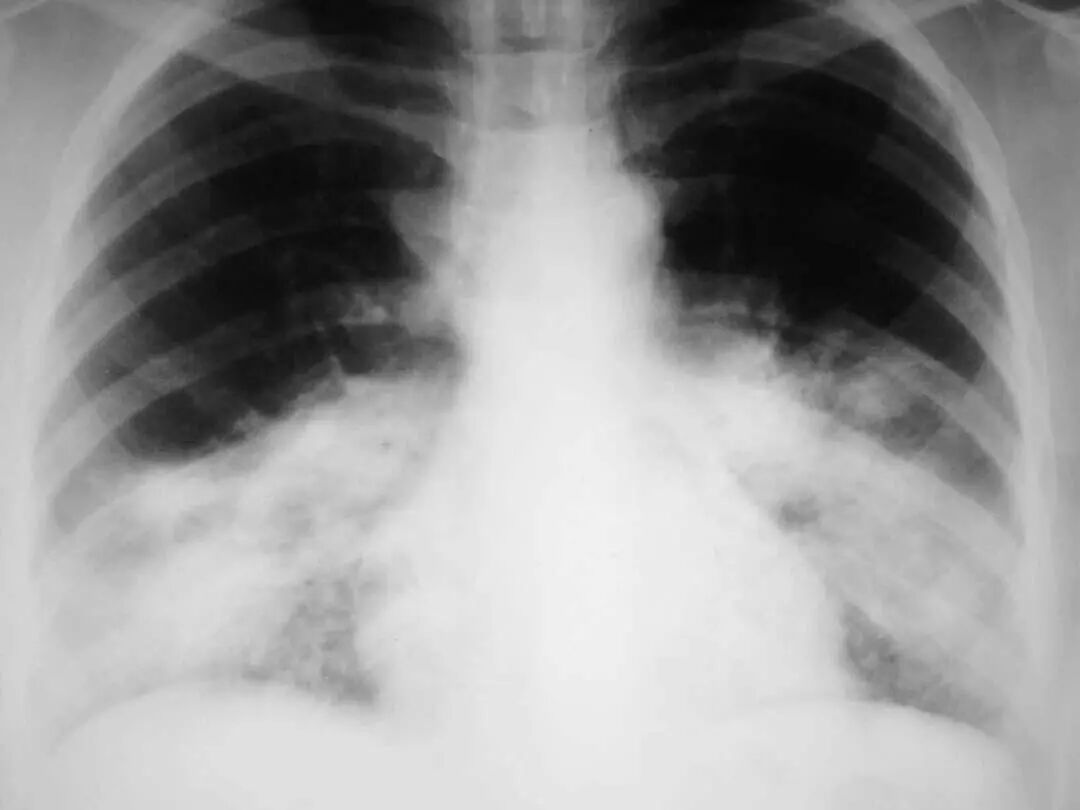

图1.4 53岁的严重军团菌肺炎患者。胸片显示双肺下叶致密实变。